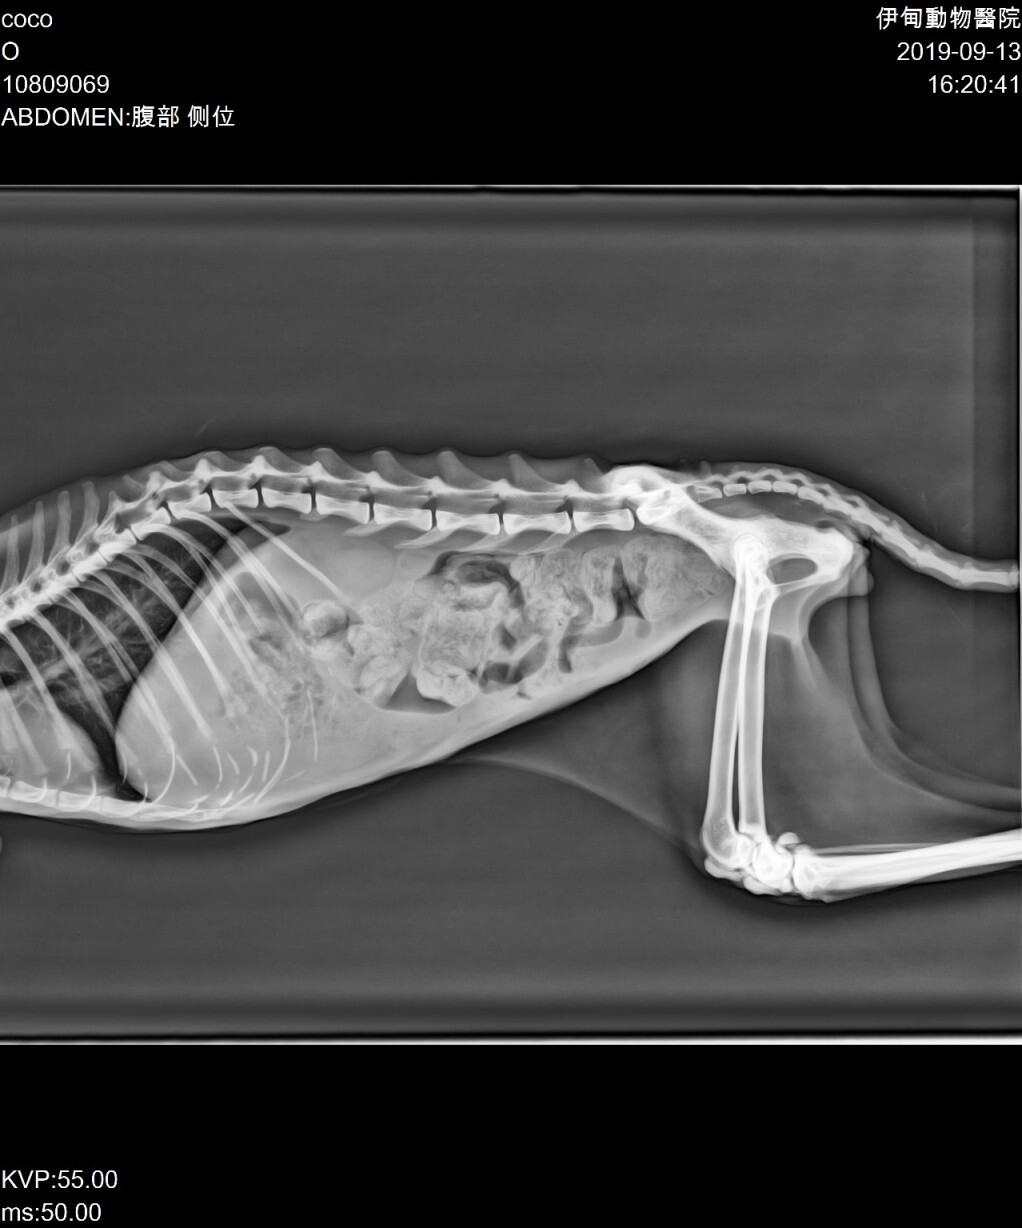

主題: 胃部淋巴腫瘤的Coco 申請者姓名: 施慧君 花色: 申請日期: 2019-11-18 13:06:23 申請者部落格: 申請者臉書網址: 所在縣市/合作醫院: 台北市/內湖維康動物醫院 治療費用: 27489元 需求人數: 59人 已結案 (2024-05-31 18:26:14) 報名人員: kara(已付款)、Kero Yen(已付款)、Jessy(已付款)、黃蔡玉英(已付款)、湘楚(已付款)、湘楚、坑長(已付款)、Heidy(已付款)、Bella Chen x2(已付款)、Shoot Yo(已付款)、彷彿是昨天(已付款)、meemee x2(已付款)、meemee x2(已付款)、Ada x10(已付款)、何偉靖(已付款)、Laura(已付款)、陳昱先 x2(已付款)、lin789 x13(已付款)、Andy chen(已付款)、Yu Ju Liu(已付款)、Hsuan(已付款)、Fatefaye Wu(已付款)、黛咪 x9(已付款)、lin789 x4(已付款)、 候補人員: 動物病情說明: Coco是社區內的流浪貓,2008年春天出生,2008年底結紮剪耳放回,一直不親人的Coco於今年夏天開始變瘦,原本體重應該有4公斤,至9月3日救援並先後帶至汐止眾新動物醫院跟台北伊甸動物醫院求診時,體重只剩下1.95公斤,血檢報告有嚴重貧血及超音波檢查懷疑胃部有腫瘤。

2019年9月18日帶至內湖維康動物醫院腫瘤門診吳鈞鴻醫師做超音波檢查及細針採樣,確定Coco的胃部出現高惡性淋巴腫瘤。

2019/09/18 腹部超音波+開始給予口服類固醇(費用$10450,志工自付)

2019/09/25 體重2.45kg,第一次酵素化療+造血針(費用$5920,申請醫助)

2019/10/02 體重2.63kg,腹部超音波+第二次酵素化療+造血針(費用$8420,申請醫助)

2019/10/09 體重2.81kg,腹部超音波+第一次口服化療+造血針(費用$4570,申請醫助)

2019/10/16 體重2.69kg,腹部超音波+第一次針劑化療+造血針(費用$7070,申請醫助)

2019/10/23 口服藥費用770,申請醫助

2019/10/30 體重2.69kg,腹部超音波+第二次口服化療(費用$4480,申請醫助)

2019/11/07 體重2.19kg,腹部超音波+第二次針劑化療+造血針(費用$8040,申請醫助)動物近況說明: 2019/11/12 因Coco胃部淋巴腫瘤控制不如預期加上嚴重貧血,晚間8點開始體溫變低,大約晚間11點離世,感謝協會提供醫助機會,讓Coco得到腫瘤治療的機會,整個醫療期間曾Coco開心吃喝,於10月中體重上升至2.81公斤,但是於第2次口服化療後病況開始走下坡,雖然最終的結果還是離開,但是起碼我們努力過!